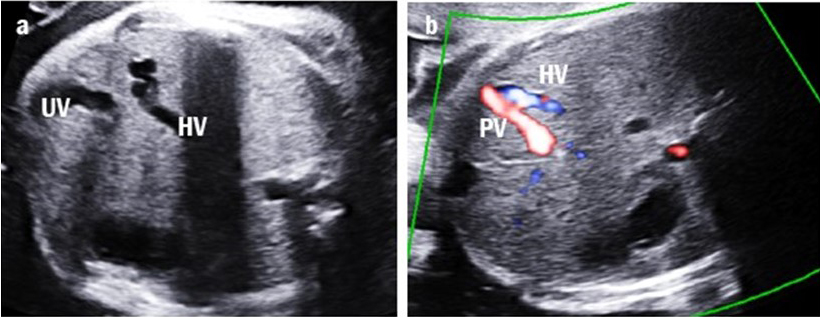

Four cases were classified as type IIIa UPSVS. They showed an abnormal connection between the PV and hepatic vein, which was observed as a tortuous and engorged vessel in the fetal liver (Fig. 4). However, the umbilical-portal-DV complex remained intact. Among these cases, three (75%) had birth weights below the 10th percentile and all had transient mild hyperammonemia. More importantly, none of them required shunt ligation surgery or liver transplantation.

Fig. 4.Intrahepatic portal-systemic shunt in case 11. (a) The tortuous and engorged hepatic vein (HV) is shown. (b) The intrahepatic portal vein (PV) is connected to the HV.

One case of type IIIb UPSVS was identified (case 14). Prenatal ultrasonography revealed an abnormal tortuous vessel communicating between the PV and IVC (Fig. 5). Due to this shunting flow, the IVC became enlarged; otherwise, the umbilical-portal-DV complex was intact. The fetus was below the 3rd percentile and had both cardiac and extra-cardiac anomalies. Additionally, the karyotype results showed an unbalanced (X;22) translocation. The neonate suffered from bronchial stenosis and died due to pulmonary hypertension and heart failure at the age of three months.

Fig. 5.Extrahepatic portal-systemic shunt in case 14. The portal vein (PV) is connected to the inferior vena cava (IVC).